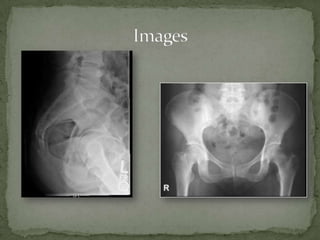

A 56-year-old female presented to urgent care with pain in her tailbone after tripping and landing on her buttocks. On examination, she had tenderness over her sacrum and pain with hip flexion and defecation. A rectal exam also caused significant pain on posterior compression, suggesting a coccyx fracture. Conservative management including analgesics, stool softeners, bed rest, and follow-up in 2-3 weeks was recommended.